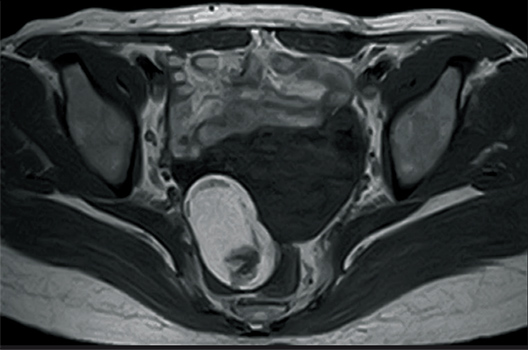

T2WI